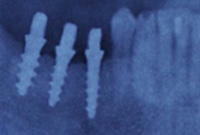

Impianti dentali

Implantologia immediataQuante visite dovrò fare per un restauro completo della bocca?